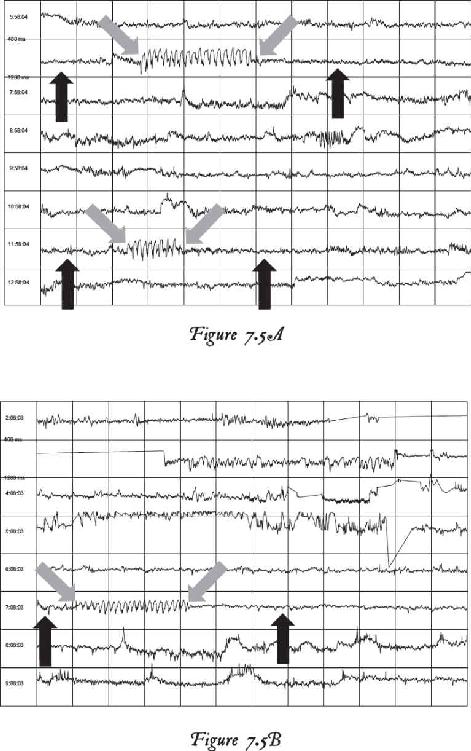

We have thousands and thousands of brain scans that prove those changes were not just imagined in their minds but actually took place in their brains. Several of the students we measured accomplished those changes within four days (the length of our advanced workshops). The scientific teams I’ve assembled have taken brain scan recordings using quantitative electroencephalogram (EEG) measurements before and after workshops as well as real-time measurements during the meditations and practices themselves. I was not only impressed with the changes, but shocked by them—they were that dramatic.

At the end of 2013, something mysterious started occurring. We started seeing brain scan recordings that puzzled the researchers and neuroscientists who came to our events to study my work. The high amount of energy in the brain that we were recording while a student was in certain meditations had never been recorded up until this point. And yet we were seeing these off-the-charts readings again and again.

When we interviewed the participants, they reported that their subjective experience during the meditation was very real and mystical, and that this either profoundly changed their view of the world or dramatically improved their health. I knew in those moments that these participants were having transcendental experiences in their inner world of meditation that were more real than anything they had ever experienced in their outer world. And we were capturing those subjective experiences objectively.

That has become a new normal for us now, and as a matter of fact, we can often predict when these high amplitudes of energy in the brain will occur, based on certain indicators and signs that we have seen for years now. In these pages, I want to demystify what it is to have an interdimensional experience as well as provide the science, biology, and chemistry of the organs, systems, and neurotransmitters that make this happen. It is my hope that this information will give you a road map for how to create such experiences for yourself.